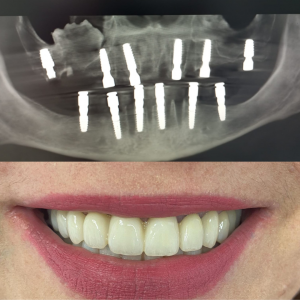

Después del Tratamiento

Tras la colocación de los implantes y las prótesis provisionales, el paciente recuperó la función completa y una sonrisa estética en solo 24 horas. Las radiografías muestran una integración adecuada de los implantes y una mejora significativa en la estructura ósea.